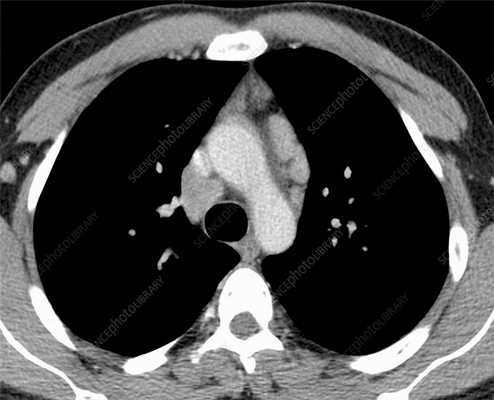

КТ ОГК. Объемное образование в средостении (патологически измененный лимфоузел), подтвержденная лимфома.

Лимфома легких на КТ

Признаки лимфомы легких особенно выражены на четвертой стадии заболевания, когда болезнь поражает дыхательный орган. На КТ при этом будут видны увеличенные лимфоузлы, формирующие цепочки, конгломераты. При этом у пациента может также наблюдаться отек легких. Однако высокая разрешающая способность КТ позволяет выявить лимфому на ранней, первой стадии.

На КТ лимфомы, как и любые уплотнения, визуализируются сравнительно более светлым цветом. В норме воздушная легочная паренхима практически однородного темного цвета. Иногда таких уплотнений несколько и они диссеминированны. Контуры лимфомы четкие и ровные. Вокруг патологических очагов обнаруживаются участки «матового стекла».